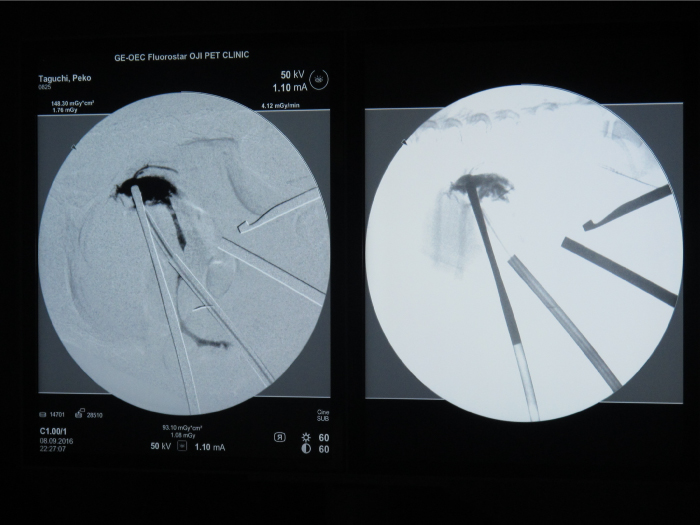

胆嚢の通路がちゃんと開通しているのか調べるために造影検査をしています。

この処置をすることで洗浄の効果と詰まりを確認することができます。

総胆洗浄をして詰まりがないかまずは確認します。(右)

きれいに開通していました。鉗子が大きく感じますが体が小さいので大きく見えます。

詰まりがないかを透視で確認しています。